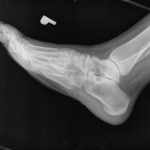

Po analizie stwierdziłem kompletną destrukcję kości skokowej po złamaniu nie rozpoznanym

pierwotnie.

Dotarła do mnie w takim stanie jak na pierwszych zdjęciach.

przed operacją chora stopa

przed operacją